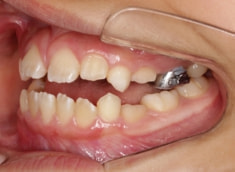

治療前